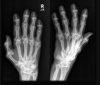

Fratura de Bennett

Fratura da base do primeiro metacarpo;

Intra-articular;

Dois fragmentos.